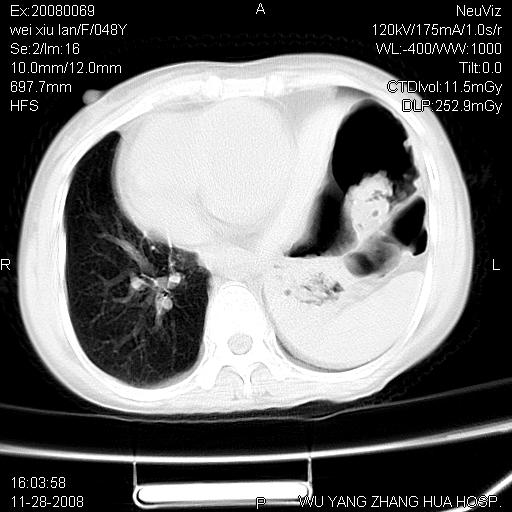

标题: CT16847:女,48岁,咳嗽,发热两日,平常偶有上腹部不适。 [打印本页]

标题: CT16847:女,48岁,咳嗽,发热两日,平常偶有上腹部不适。

能否考虑食管裂孔疝?请老师们多多指教。

这个是左侧膈膨升伴不完全性胃翻转,手术将松弛的左横膈膜折叠缝合即解决问题。

支持左侧膈疝,心脏受压右移.

胃、脾脏及部分肠管明显升高,并压迫心脏移位,

首先考虑:左侧膈疝。

左侧胸腔内见胃肠及脾脏影

支持膈疝